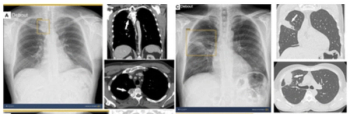

Emerging research suggests that adjunctive artificial intelligence (AI) improves sensitivity for a variety of abnormalities on chest X-rays regardless of radiologist experience level, including an average 26 percent increase in sensitivity for pneumothorax.

Artificial intelligence (AI) assessments of chest X-rays identified 28 percent of a 17,000 plus cohort of never-smokers as being at high-risk for lung cancer, according to research to be presented at the annual Radiological Society of North America (RSNA) conference next week.